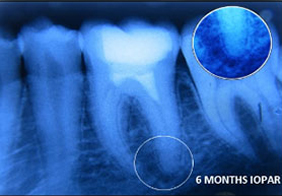

PRF Mediated REP in 21 with 18 Months Follow Up

Complete Bony Healing, Apex Closed, Lateral Wall Thickening- 15.5%

PRP Mediated REP in 21 with 18 months follow up

Bone healing, Apical PDL formed, Apex Closed, Calcific Bridge formed in 21.

Vitality Positive

PRF Mediated REP in 21 with 26 Months Follow Up

Complete Bony Healing, Apex Closed, Lateral Dentinal Wall Thickened, PDL Apically